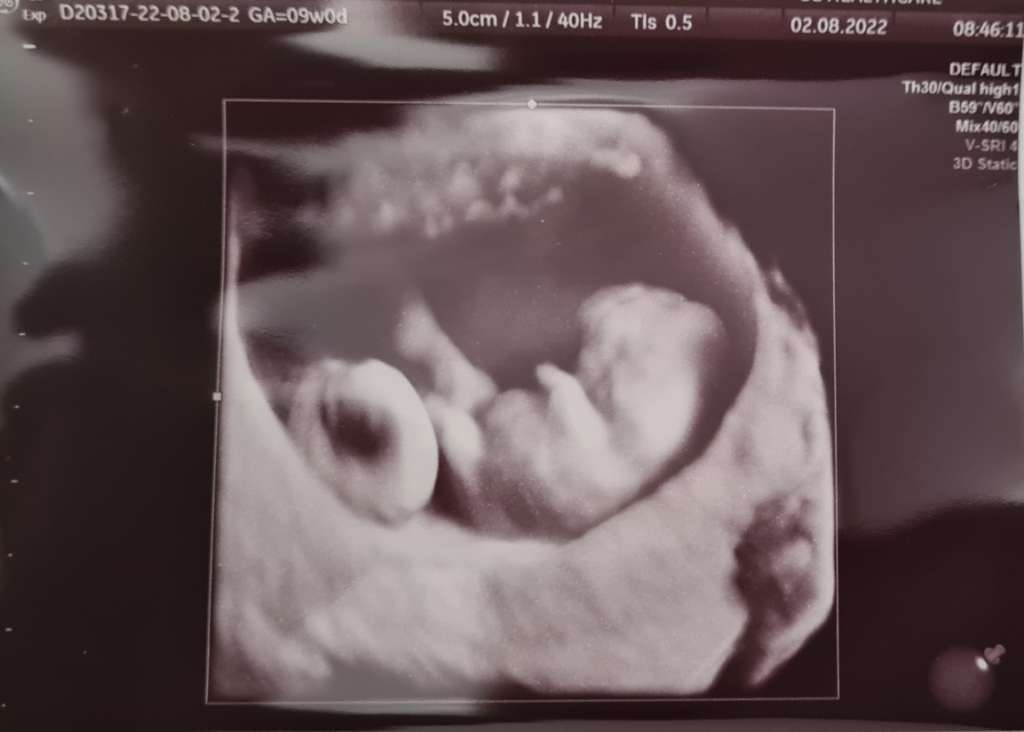

Hejka Kochane! Z całego serduszka dziękuję za wszystkie mocno zaciśnięte kciukasy. Przydały się jak nie wiem ❤️ Prawie zemdlalam siadając na fotel. Okazało się, że owszem cialko żółte nie jest najmniejsze, ale Pani Doktor (a jej akurat ufam) powiedziała że wielkość ok- czasem jest skorelowana z wadami genetycznymi, ale to kompletnie nie jest etap na którym cokolwiek można wyrokować. Czasem nie znaczy zawsze. Genetyje będziemy oceniać dopiero później jak już wszelkie struktury będą widoczne. Narazie powiedziała zeby to cialko zolte w ogóle z głowy wyrzucic- obraz ciałka ciążowego, zarodka, kształt wszystkiego wygląda naprawdę bardzo ładnie. Nie ma też już śladów plamien, krwawienia, szyjka macicy wygląda ok i struktura brzucha w badaniu manualnym tez wygląda ok 🥰 powiedziała że nie raz już widziała większe cialko i to o niczym nie świadczyło tak długo jak jego obraz u obraz całej reszty był w porządku... taki kamień z serca że aż mi zły poleciały 😭 powiedziała że na tym etapie wszystko wygląda ksiazkowo- maluch rośnie zgodnie z planem, serduszko biję jak dzwon. Powiedziała tez że większość poronień uwarunkowanych dysfunkcja ciałka żółtego dzieje się do 9tc (my już go zaczelismy) wiec ona jest dobrej myśli 🥰 Nasz mały człowieczek ma 2,33 cm i srduszko bije 176/min ❤️ Partner aż po prostu w skowronkach jak zobaczył wreszcie naszego małego fasolka 🥰 Przesyłam wam tysiące uścisków i podziękowania za wszelkie słowa otuchy i kciuki ❤️ jesteście najlepsze! Ja teraz staram się nastawiać pozytywnie 😊 i 3mam się tego ze musi być dobrze! I wierzę że badania genetyczne tez wyjdą ok ❤️

• 6e6cdddd-28a2-4f14-8ebe-66d9cae2a915.jpeg

6e6cdddd-28a2-4f14-8ebe-66d9cae2a915.jpeg

33,5 KB · Wyświetleń: 122